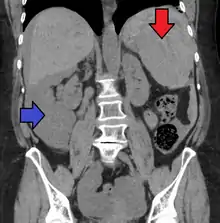

| Spleen ruptured by trauma | |

Splenic rupture is usually evaluated by FAST ultrasound of the abdomen.[3] Generally this is not specific to splenic injury; however, it is useful to determine the presence of free floating blood in the peritoneum.[3] A diagnostic peritoneal lavage, while not ideal, may be used to evaluate the presence of internal bleeding a person who is hemodynamically unstable.[4] The FAST exam typically serves to evaluate the need to perform a CT scan.[4] Computed tomography with IV contrast is the preferred imaging study as it can provide high quality images of the full peritoneal cavity.[3]